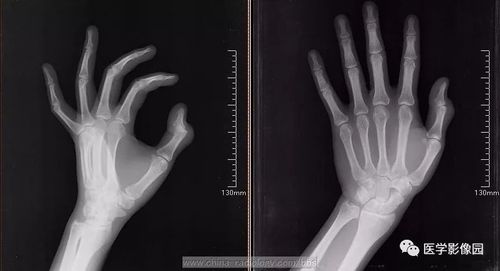

【筋骨堂】手指关节疼痛,变形是骨关节炎还是类风湿?

请教,手指关节,变形,疼痛,是什么原因.